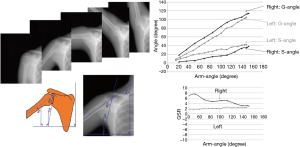

Sakuda et al. developed a sequential X-ray imaging technique and a functional analysis technique for the quantitative assessment of shoulder joint movement (Figure 3) (9). During arm elevation, shoulder joint movement displays a characteristic rhythm. Specifically, the angle between the humerus and the scapula (glenohumeral angle) and the angle between the scapula and the axis of the thorax (scapulothoracic angle) are normally in a fixed 2:1 ratio regardless of the angle of arm elevation (scapulohumeral rhythm: G/S). Changes in this rhythm are useful in discovering abnormalities in the shoulder joint and assessing severity. Therefore, this method is effective in assisting therapeutic strategy determination and monitoring therapeutic progress. The total exposure dose was almost equivalent to that of the two projections in conventional shoulder imaging (0.4 mGy) (9).

There are many reasons for performing orthopedic assessments of shoulder kinetics, and the use of various modalities has been reported. For example, in their study on an X-ray TV system, Inman et al. reported that the field of view (FOV) is narrow and that the analytical accuracy is limited due to poor image quality (10). In their attempt to perform highly accurate assessments using MRI, Roberts et al. reported that because the procedure is time consuming and expensive, it is not clinically practical (11). Although sonographic imaging techniques are simple, because the FOV is narrow, the ability to assess large joint kinetics is limited (12). There have been multiple reports on methods of measuring kinetics of joint from the surface of the body using videometers and goniometers; however, these reports are limited by their inability to directly assess and analyze intra-articular structures (13-15).